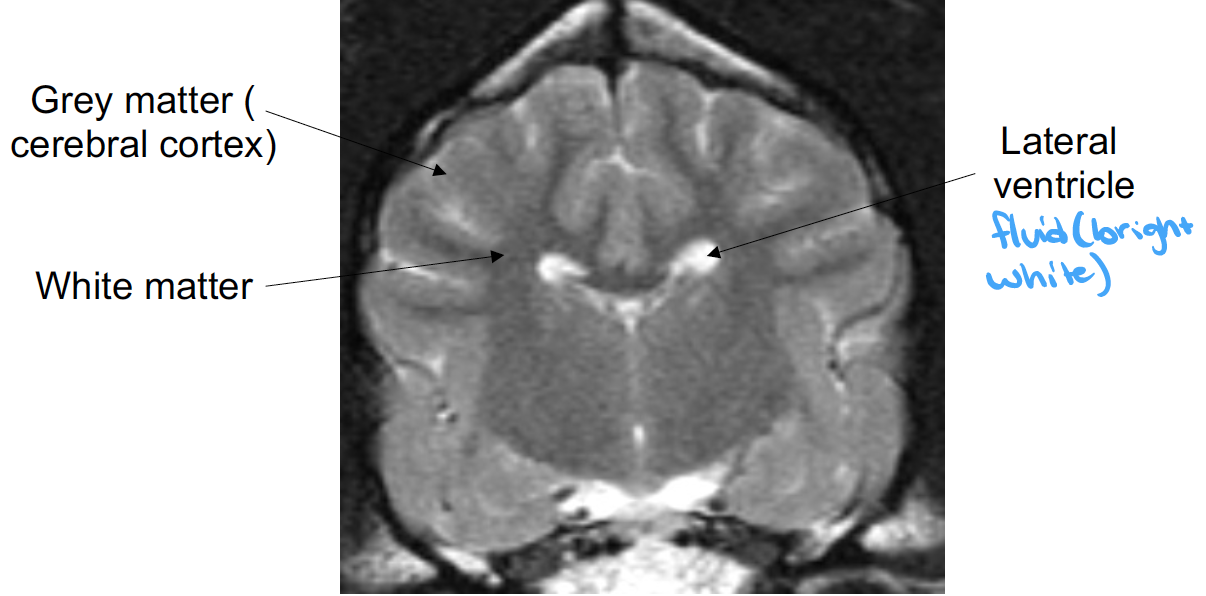

what is the cerebral hemisphere made up of

surface grey matter –> called cerebral cortex

underlying white matter and deep masses of grey matter –> called basal nuclei

each hemisphere contains a cavity –> lateral ventricle

what structures are shown